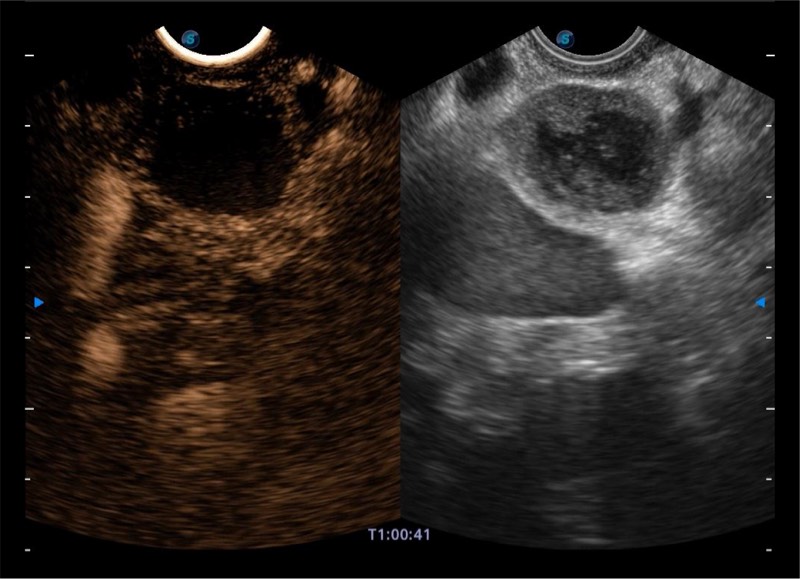

基于二十年的超声技术积累,诸侯快讯官网提供了最新一代的独立超声主机,在提供高质量图像的同时满足多学科使用。具备常见多普勒技术并提供弹性成像、声学造影等高端影像技术。新一代传感器具有更强的抗干扰能力并减少图像伪影。